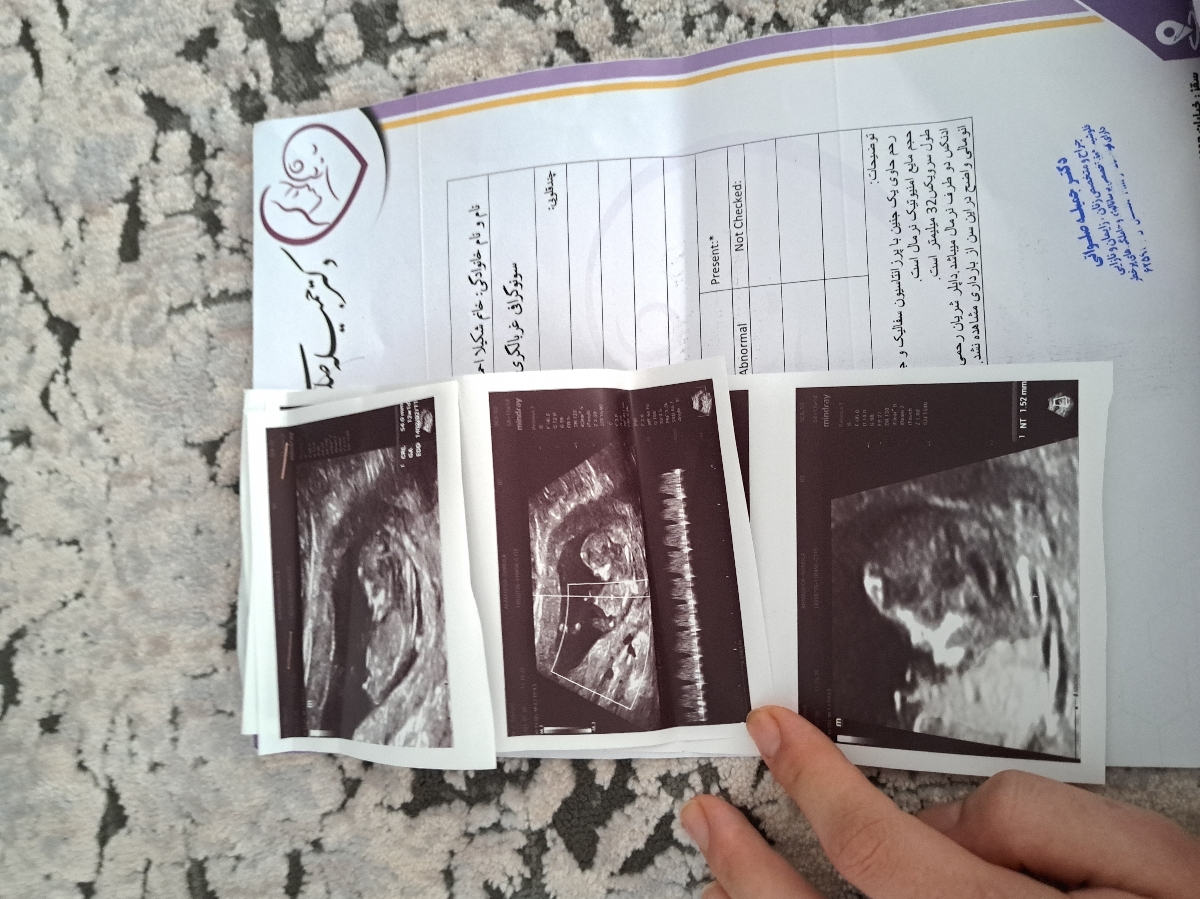

سلام خسته نباشید ببخشید ایا مشکلی تو جواب ازمایشم نیست ممنون میشم جوتب بدید و اینکه من دو هفته قبل از سونو ان تی رفتم و گفتن طول سرویکسم ۲۹ هستش ولی این دفعه ک رفتم ۳۲ بود ایا خوبه یا هنوز کمه و بمن گفتن ک جفتم پایینه و باید استراحت باشم ایا جفت بالامیره یا همینطوری میمونه😢

عزیزم در سونوگرافی شما تمام موارد بررسی شده از جمله وضعیتجنین، حجم مایع آمنیوتیک، ضربان قلب و همچنین میزان ان تی (NT) در محدوده نرمال قرار دارد و از این بابت جای نگرانی نیست. در مورد جفت نیز جایگاه آن پرویا یعنی سرراهی گزارش شده است اما سرراهی کامل نیست. در چنین مواردی در اغلب مواقع با افزایش سن حاملگی و بزرگ شدن رحم، دیواره های آن کشیده شده و بنابراین جفت نیز به سمت بالا کشیده می شود و مشکلساز نخواهد شد اما فعلا چون طول سرویکس همچنان رو به پایین است بهتر است تا میزان استراحت خود را بسیار بسیار افزایش دهید. و اگر استراحت رو به مطلق داشته باشید بهتر است. تا جایی که میتوانید اصلا از پله بالا و پایین نروید. سفر برایتان ممنوع است. از انجام دادن کارهای سنگین و بلند کردن وسایل با وزن بالا اجتناب کنید. پیاده روی طولانی نداشته باشید و تحریک و دستکاری نوک سینه ها و دخول نیز ممنوع است. همچنین شخص شما نباید به ارگاسم برسید. بهعلاوه ریسک محاسبه شده برای سندروم های ژنتیکی تریزومی ۲۱ و تریزومی ۱۸ و 13 همگی در محدوده کم خطر قرار داشته و منفی هستند. در حال حاضر نیاز به هیچ بررسی دیگری نیست جان دلم و صرفاً در هفته هجده بارداری مانند تمامی مادرانی که در محدوده کم خطر قرار دارند، سونوگرافی آنومالی اسکن برای ارزیابی ساختارهای بدن جنین و همچنین آزمایش Ntd screen برای ارزیابی اختلالات لوله عصبی (این بررسی ضرورت جذب انجام ندارد و در صورت صلاحدید پزشکتان درخواست گردد) را انجام دهید💞